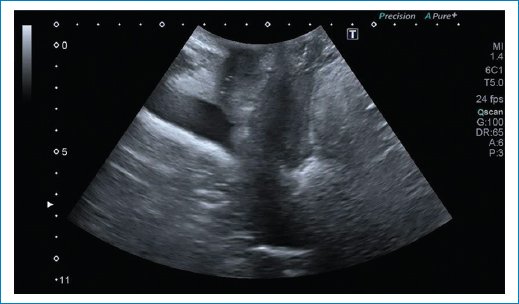

• Ángulo retrovesical (90-120°): si es abierto es más probable que la paciente tenga síntomas de incontinencia y si es cerrado de disfunción al vaciado (Fig. 8).

Figura 8. Se observa un ángulo retrovesical abierto mayor a 120 grados, con mayor probabilidad de incontinencia.